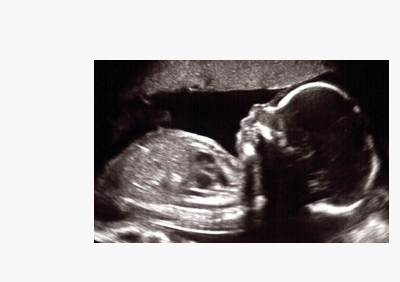

USG ANOMALY SCAN

Discover the vital insights a USG Anomaly Scan provides during your pregnancy! Typically performed between 18 and 22 weeks, this ultrasound examines your baby’s growth and anatomy, helping identify potential structural abnormalities early. It confirms healthy development and supports informed decision-making for parents and healthcare teams. This essential part of prenatal care assesses major organs and checks for congenital conditions. Learn how this safe, painless procedure can enhance your pregnancy journey!